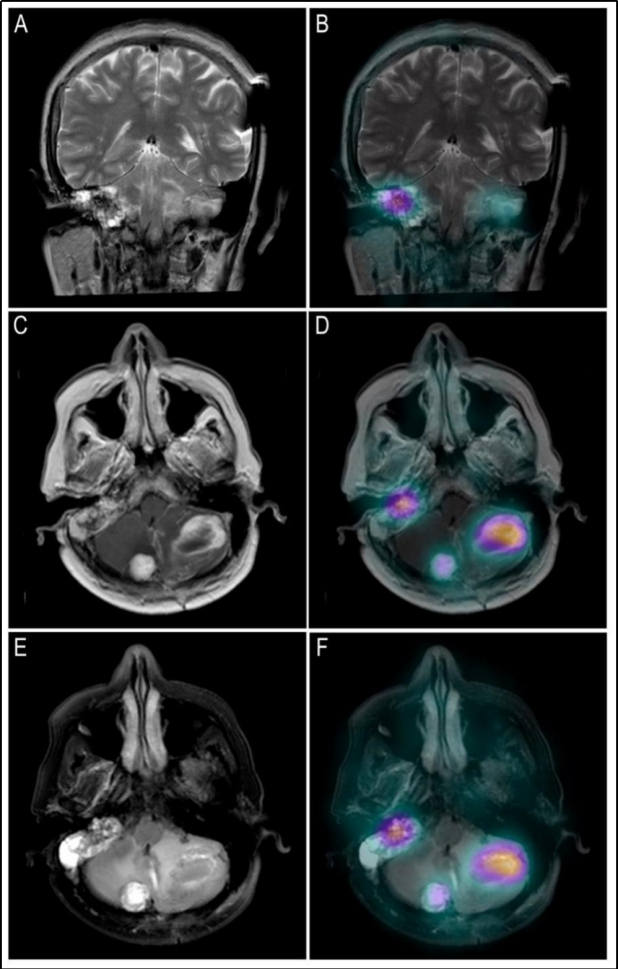

En las imágenes planares se observan múltiples áreas de captación anormal en la fosa posterior y en el aspecto lateral del hilio renal derecho (fig. 1). Se identifican tres lesiones cerebelosas con componente sólido realzante y quístico, altamente vascularizadas, que presentan aumento de perfusión y generan edema extenso obliterando el cuarto ventrículo, consistentes con hemangioblastomas (fig. 2). Existe otra lesión que genera invasión ósea de la mastoides con compromiso del oído interno; en la RM es isointensa e hiperintensa en las secuencias T1, hiperintensa en las secuencias T2, con captación del medio de contraste, por tumor del saco endolinfático (fig. 2). En la valoración de la cavidad abdominal se detecta una lesión sólida en la cabeza/proceso uncinado del páncreas, hipodensa respecto al resto del parénquima, compatible con tumor neuroendocrino (fig. 3).